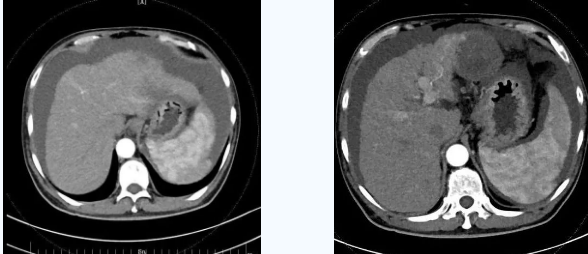

55歲的秦先生,于2021年10月被確診為肝癌晚期、慢性腎功能不全尿毒癥期,一直在口服靶向藥物進(jìn)行治療,規(guī)律行腎透析治療。直至今年4月因肝癌破裂出血行肝動(dòng)脈分支栓塞止血術(shù)后不久,秦先生開始出現(xiàn)了反復(fù)大量腹水,只能先暫停癌癥治療,解決腹水問題??墒乔叵壬奶幈疾▽めt(yī),腹水仍然沒有得到有效控制,于是在家人的多方咨詢打聽下,慕名來到西安國(guó)際醫(yī)學(xué)中心醫(yī)院。

入院后,消化內(nèi)科五病區(qū)韓國(guó)宏院長(zhǎng)帶領(lǐng)團(tuán)隊(duì)對(duì)患者做了深入的檢查,檢查后發(fā)現(xiàn)患者“肝硬化失代償期、頑固性腹水、原發(fā)性肝癌、慢性腎功能不全尿毒癥期、2型糖尿病、高血壓2級(jí)”等病癥,韓院長(zhǎng)在對(duì)患者的病情進(jìn)行反復(fù)評(píng)估分析后表示,首先要明確患者目前腎透析后,仍然是大量腹水、無尿,那么腹水是肝源性的還是腎源性的,遂請(qǐng)多學(xué)科會(huì)診,結(jié)合相關(guān)檢查后明確,秦先生目前的大量腹水是由于門脈高壓導(dǎo)致的頑固性腹水,只有先解決門脈高壓導(dǎo)致的頑固性腹水,才可以繼續(xù)進(jìn)行癌癥治療,于是,韓院長(zhǎng)決定為患者實(shí)施TIPS手術(shù)。

由于大量腹水、晚期肝癌加上尿毒癥等的綜合病癥,手術(shù)難度和危險(xiǎn)系數(shù)都比平常增加了幾倍,面對(duì)這樣的情況,術(shù)前韓國(guó)宏院長(zhǎng)帶著團(tuán)隊(duì)反復(fù)分析討論,全面評(píng)估,在患者的各項(xiàng)指標(biāo)達(dá)到手術(shù)標(biāo)準(zhǔn)后,對(duì)患者實(shí)施了經(jīng)頸靜脈肝內(nèi)門腔靜脈分流術(shù)(TIPS),手術(shù)取得成功,術(shù)后患者恢復(fù)良好。

術(shù)后一個(gè)月秦先生來院復(fù)查,腹水已明顯較前減少,精神和飲食較術(shù)前明顯好轉(zhuǎn)。